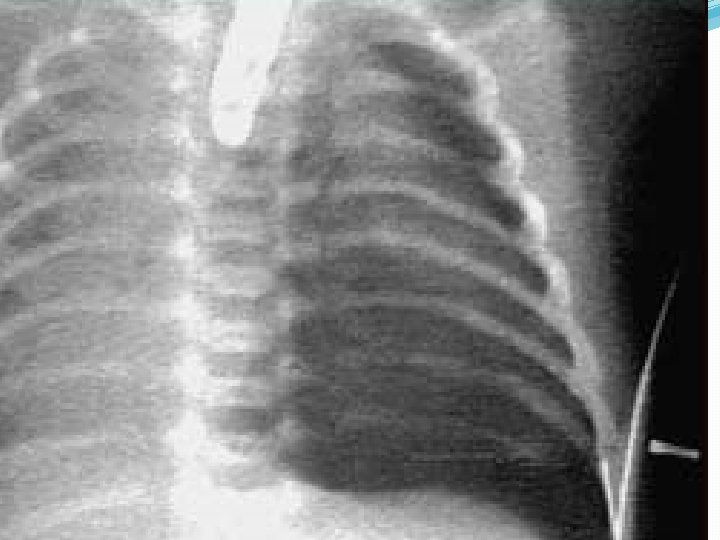

NEUMOTORAX �Aire en la cavidad pleural � Vías de entrada (siempre de la atmosfera) � A por la piel (herida de pared) � B piel y parénquima (herida) � c parénquima (trauma contuso , ruptura espontánea)

CUADRO CLINICO NEUMOTORAX �INSPECCION (disnea ) �PALPACION (disminución frémito vocal) �PERCUSION (hipertimpanismo) �AUSCULTACION (disminución murmullo vesicular)

Neumotórax a tensión �Producido por entrada de aire en la cavidad pleural, desde el exterior (neumotórax abierto, en los traumatismos penetrantes) o desde el interior.

Neumotórax a tensión � El aire entra y no sale, diferente al neumotórax compensado donde las presiones se igualan, el paciente tiene dificultad por el cuadro agudo pero no debe morir, en neumotórax a tensión se muere por colapso total.

Neumotórax a Tensión. � Las causas más comunes son la ventilación mecánica con PEEP(presión positiva al final de la espiración), el Neumotórax espontáneo con escape persistente, el trauma torácico cerrado donde la lesión pulmonar no cierra. � Se produce por escape de aire en una sola dirección, ya sea desde el pulmón o de la pared, acumulándose en la cavidad pleural, y sin posibilidad de salida, produciendo el colapso del pulmón ipsilateral. � El mediastino y la traquea se desplazan contralateralmente, comprometiendo la posibilidad de respuesta ventilatoria por parte del pulmón sano y afectando el retorno venoso. � Clínicamente se manifiesta por dificultad respiratoria, ausencia unilateral de MP, timpanismo y cianosis. Neumotórax Abierto. � Cuando el aire penetrara preferentemente por la herida al igualarse las presiones intratorácica y ambiental y ofrecer menor resistencia al paso del aire por la herida.